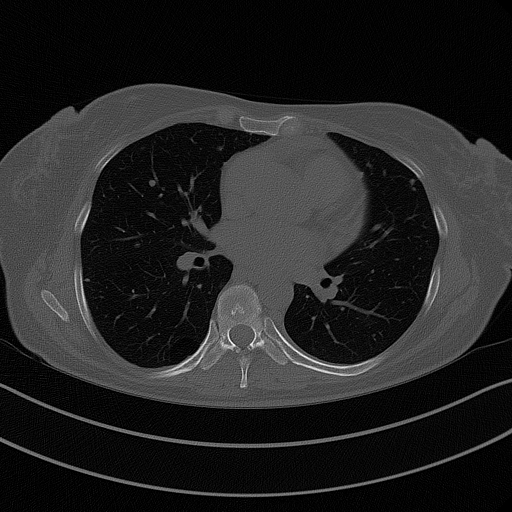

Original VENOUS CT scan

Full window (WL 1023.5, WW 4095 β†’ Low βˆ’1024, High +3071)

Actual HU range: [-1024.0, 1256.0]

Lung window (WL -600, WW 1500 β†’ Low βˆ’1350, High +150)

Actual HU range: [-1024.0, 150.0]

Mediastinum window (WL 40, WW 400 β†’ Low βˆ’160, High +240)

Actual HU range: [-160.0, 240.0]